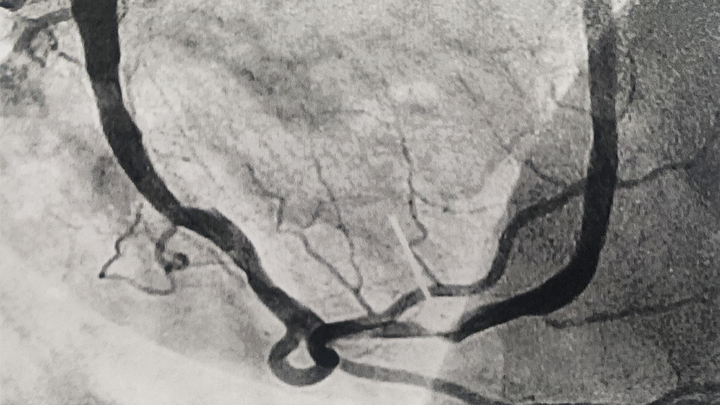

This man walked off what he knows now were possibly 3 heart attacks before the 4th had me stuffing him in the car and feeding him aspirin on the way to the hospital. This one lasted from the time he told me something wasn't right until almost 2 hours later when the surgeon in the cath lab put his 2 stents in. He can't lift more than a gallon of milk until the doctor clears him.